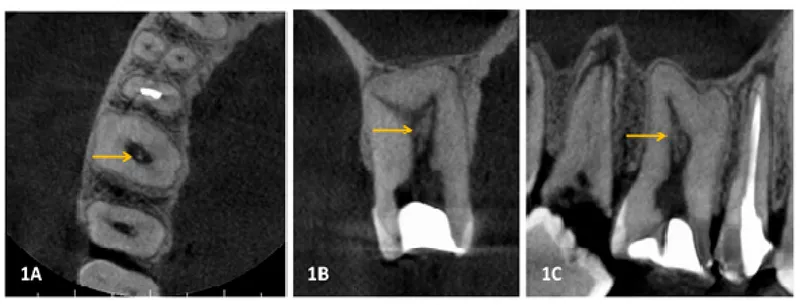

- Lateral Cephalogram, CBCT (Cone Beam Computed Tomography).

- Tooth & root morphology, pulp anatomy.

- Restorations: type, material, shape.

- Bone trabeculation, sinus patterns (e.g., maxillary).

- Pathology, anomalies, implants, foreign bodies.

- CBCT: 3D analysis, superimposition.

⭐ Unique features like morphology of tooth roots, pulp chambers, bone trabeculation, and sinus patterns visible in dental radiographs are crucial for positive identification, often as unique as fingerprints.